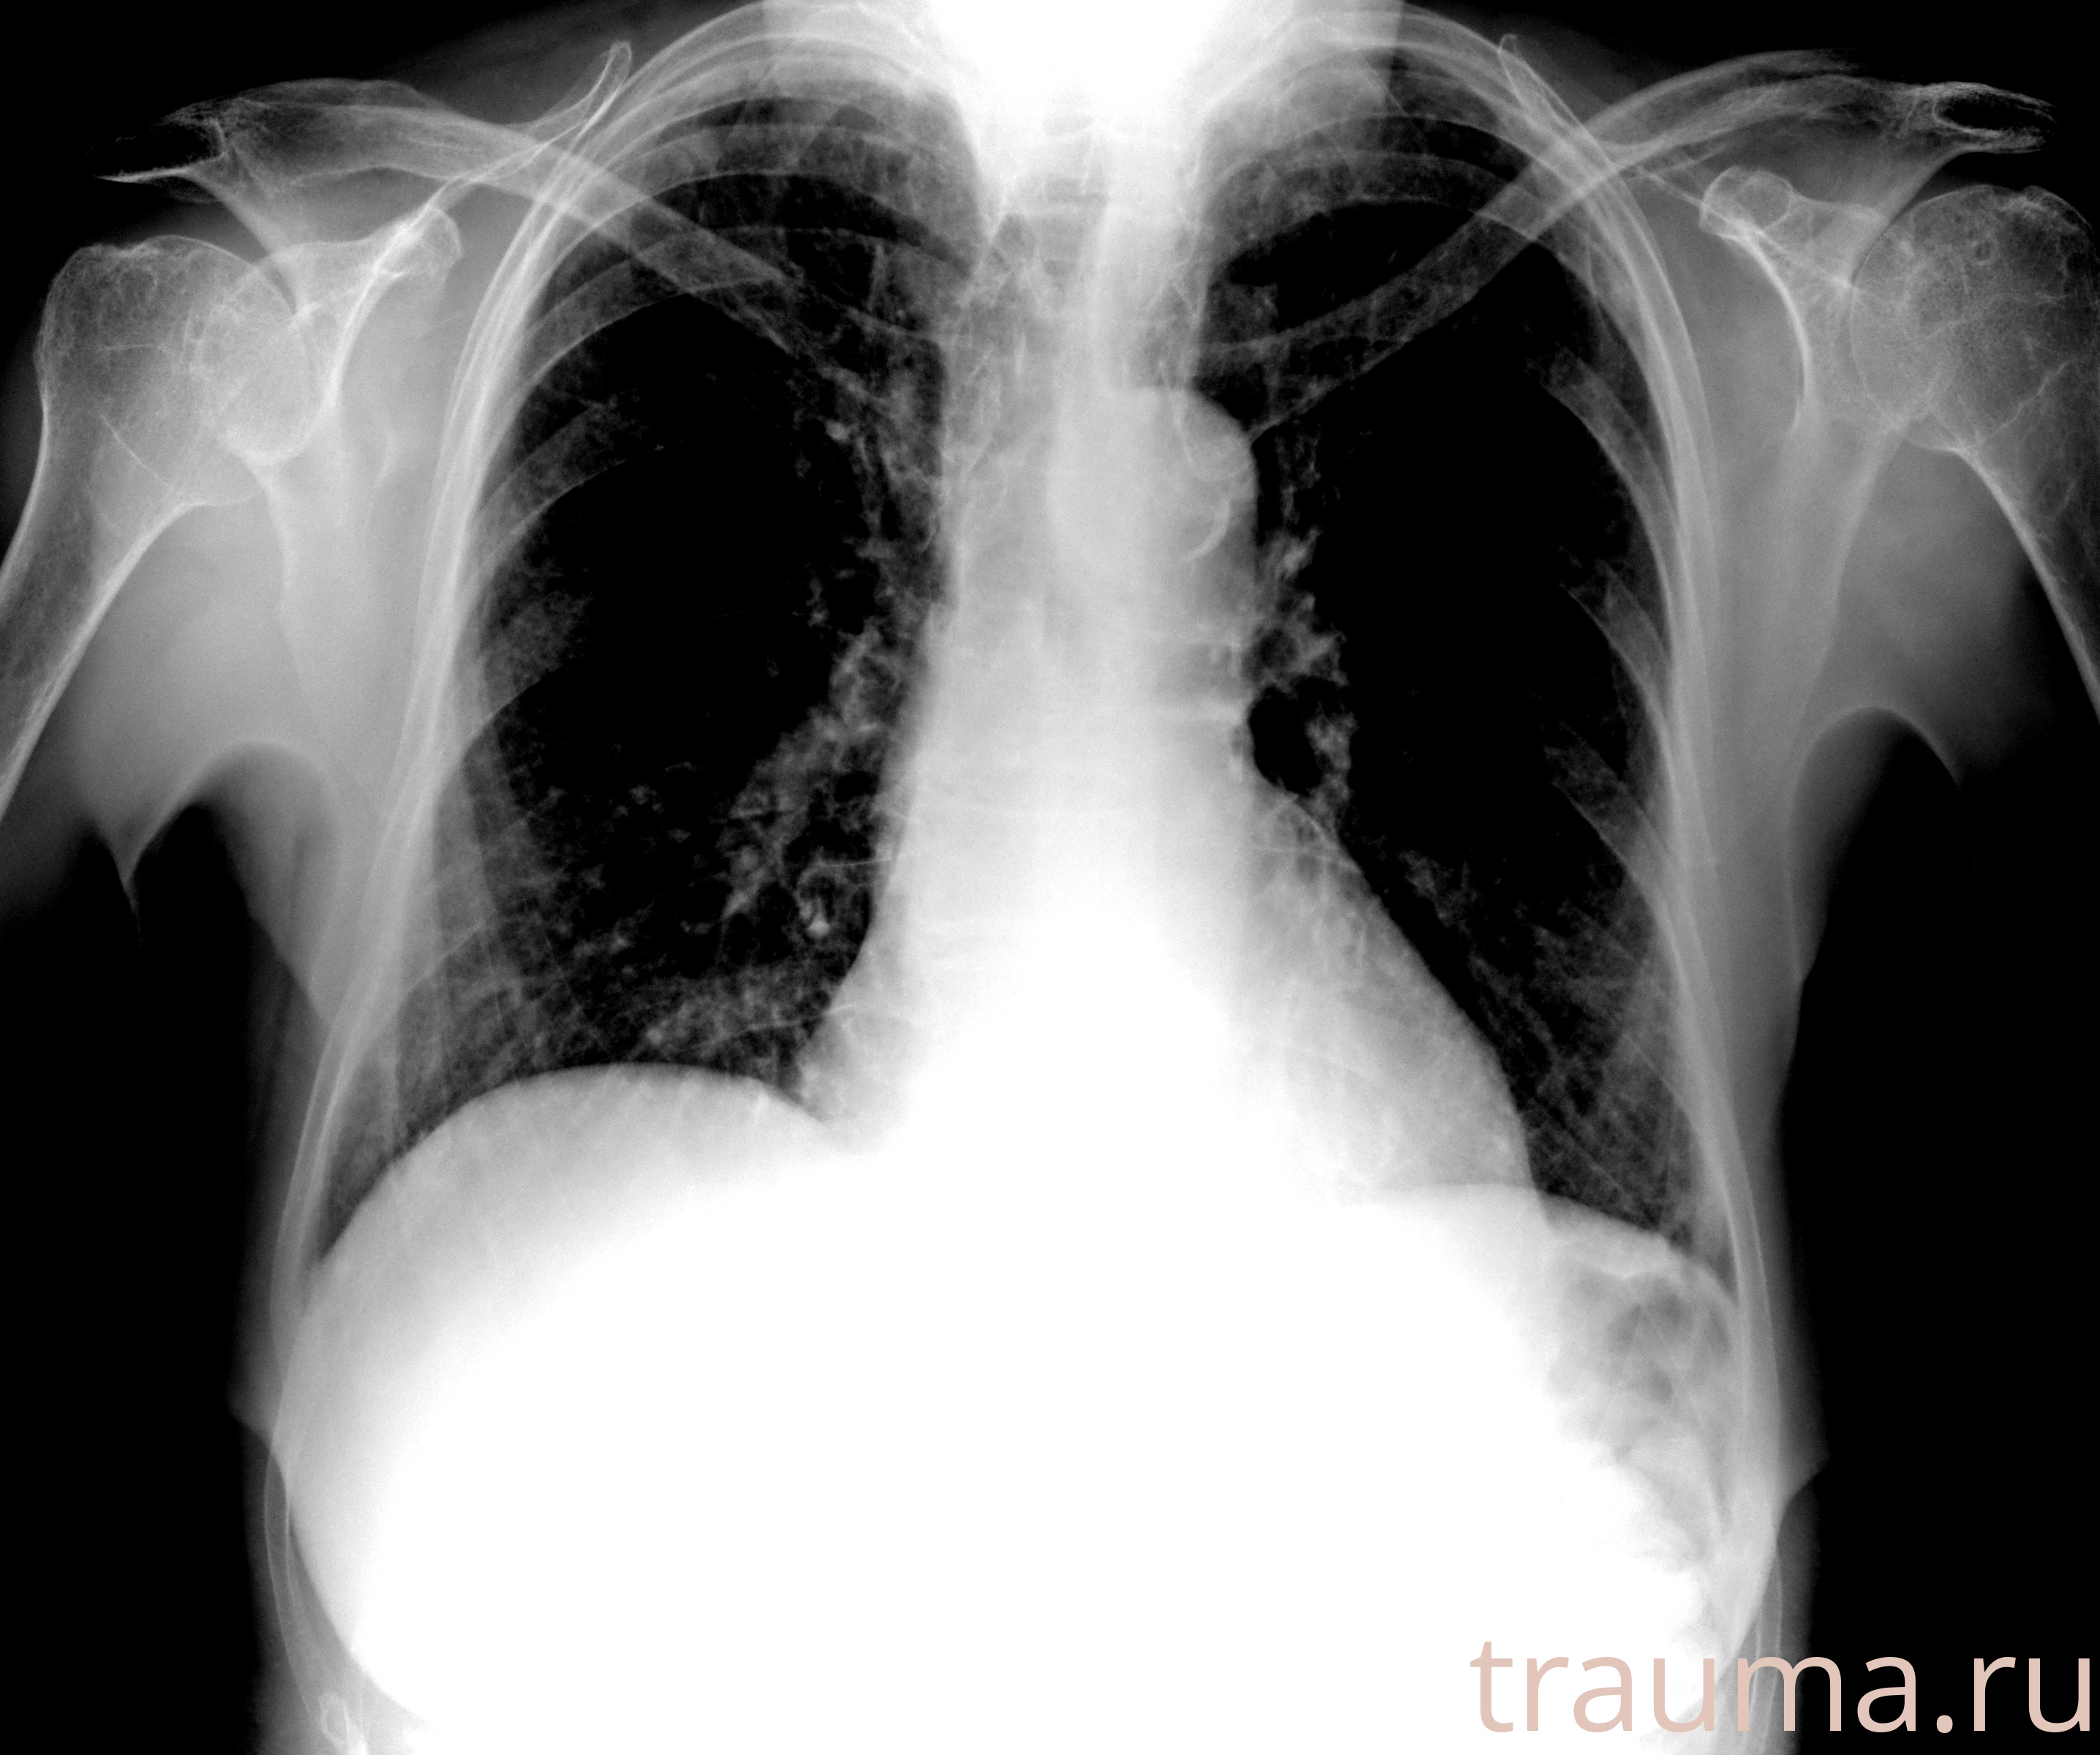

Рентгенограммы

Рентген на дому: по вашему адресу приезжает врач-рентгенолог, травматолог-ортопед с мобильным рентгеновским аппаратом, проводит диагностику травмы или заболевания, делает необходимые рентгенограммы, дает рекомендации по дальнейшему лечению. Получить качественные снимки в домашних условиях возможно благодаря уникальной методике, разработанной МосРентген Центром для института  Склифосовского